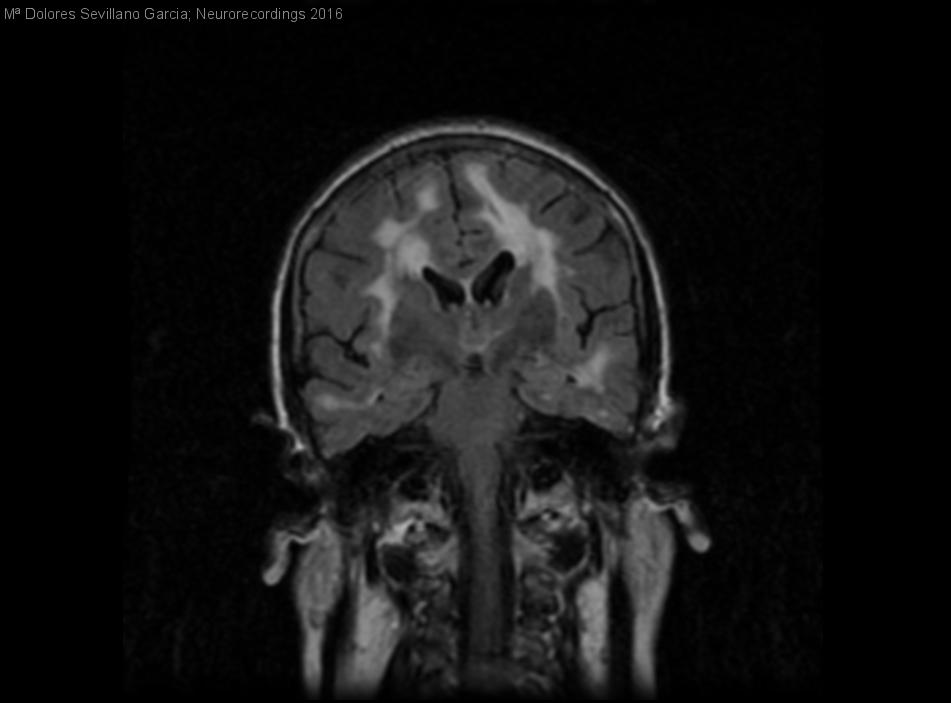

Diagnóstico final: Encefalopatia por Arteriopatia cerebral familiar- CADASIL-

Mujer de 61 años diabética, que en octubre del 2009 debuta con crisis epilépticas tónico clónicas generalizadas y disminución del nivel de conciencia persistente durante varios dias. TC cerebral se visualizan áreas hipodensas subcorticales en...